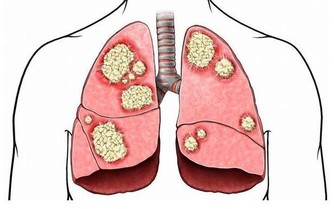

先兆症狀出現說明血管裡可能已經產生了血栓,這些小血栓當時堵塞了血管,其後又隨著血液循環轉移到末梢血管,而血管又復通,所以症狀反復出現。

之所以要立即就醫,是因為一旦發生中風,造成的後果不是致殘就是致命,但是在中風先兆出現時治療,可防止血栓進一步堵塞血管,從而可以避免中風的發生。